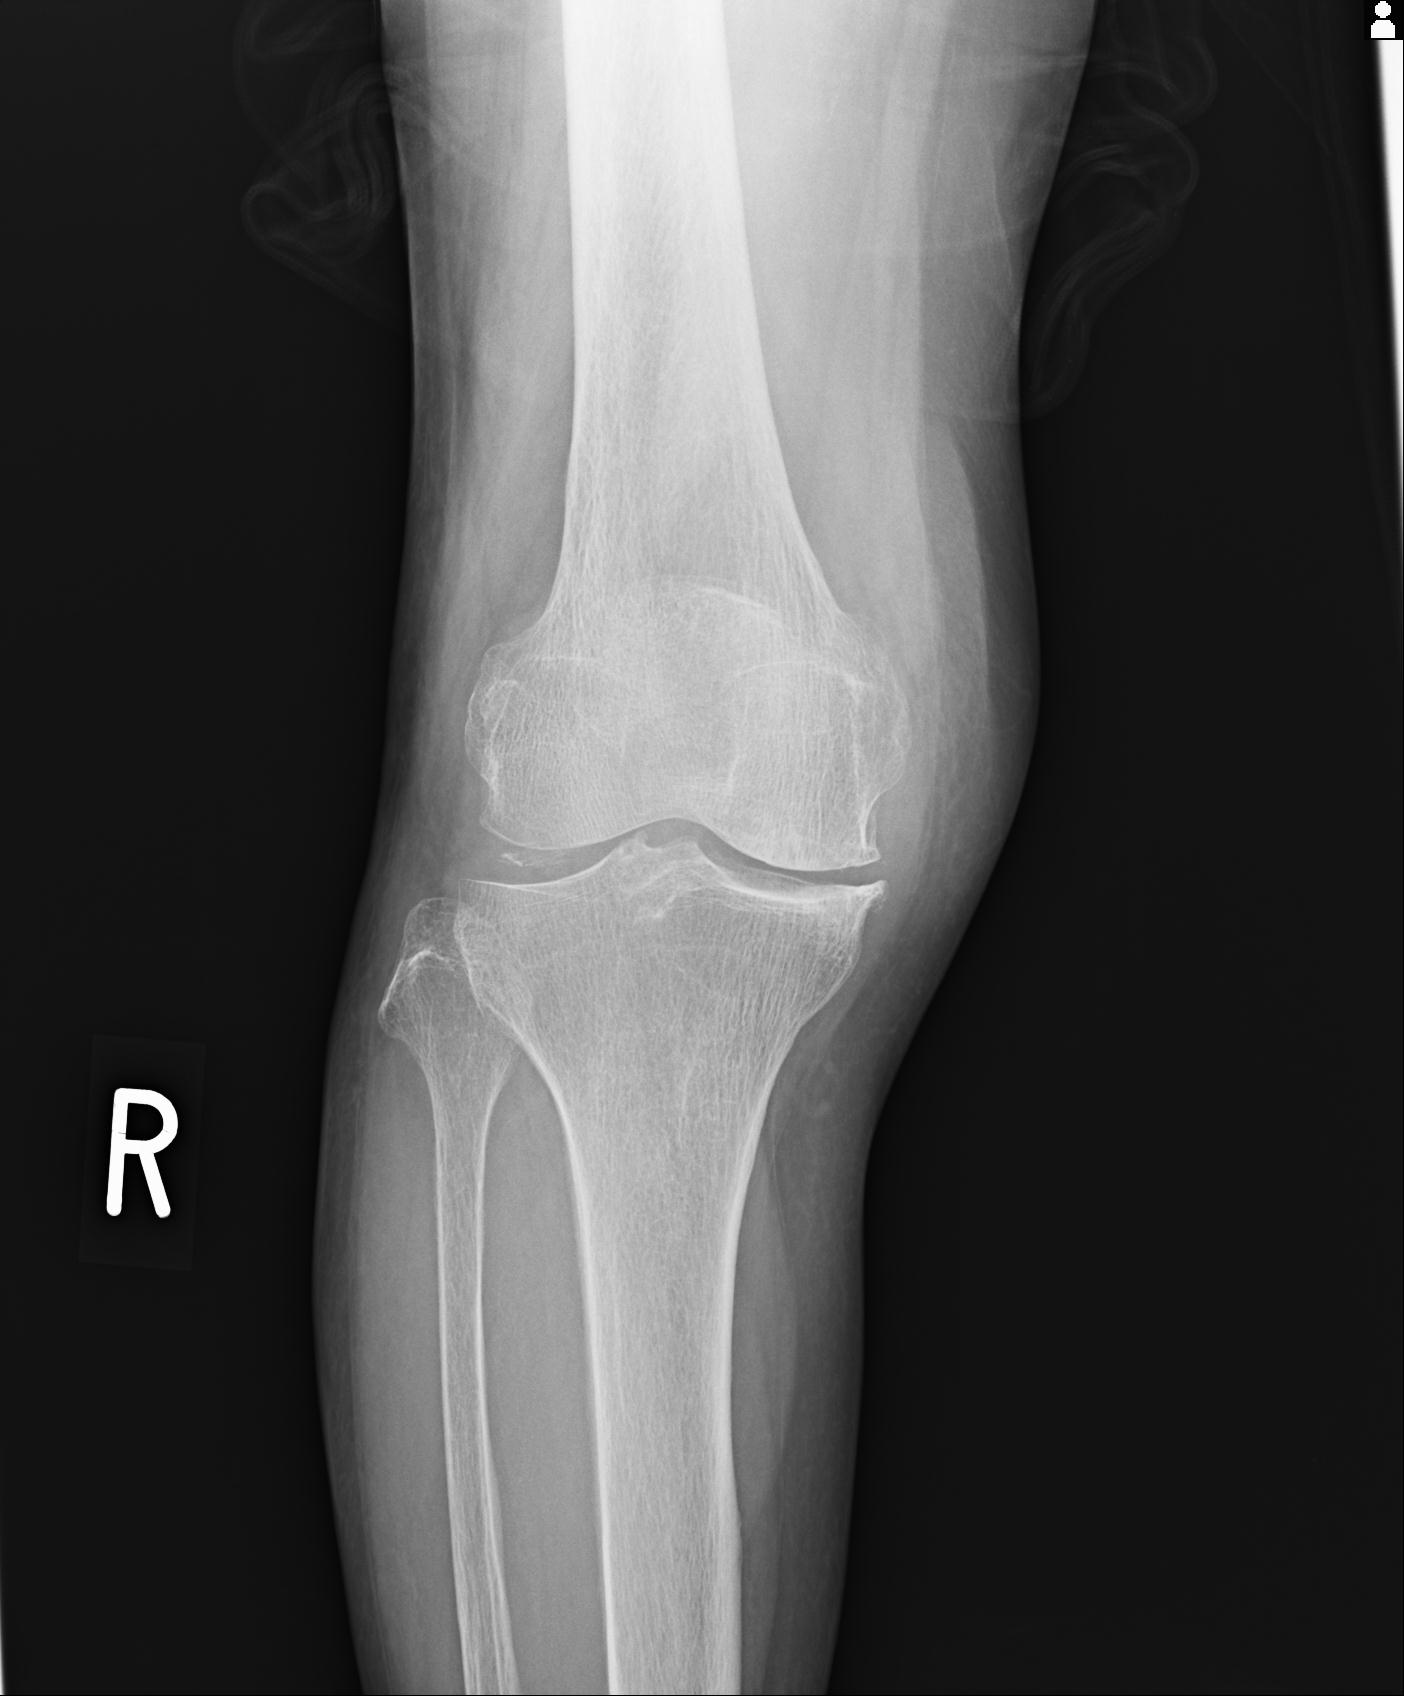

91983 11/16 左膝 2R 11/18 2R 55歳男性 脛骨骨切り術